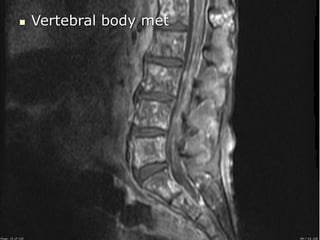

65 year old man with

Recurrent LBP that is

severe

Tumor: vertebral body

 Vertebral body met

Epidural metastasis